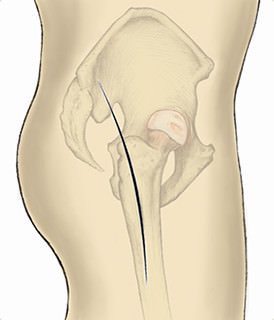

一般的によく行われている股関節の後方アプローチによる人工股関節全置換術は、最小皮膚切開手術かもしれませんが、最小侵襲手術ではありません。

現在は、皮膚切開が小さいだけではなく、さらなる低侵襲を目指し、筋肉、腱を切離しない筋肉の間から手術を行う人工股関節全置換術をMISと言います。

仰臥位手術は手術台にあおむけで寝て行う手術で、側臥位手術は手術台に横向きで寝て行う手術です。

当院では人工股関節のインプラント設置(特にカップの設置)がより正確に行える仰臥位手術を基本としており、基本的にはALSによる人工股関節全置換術を行っています。